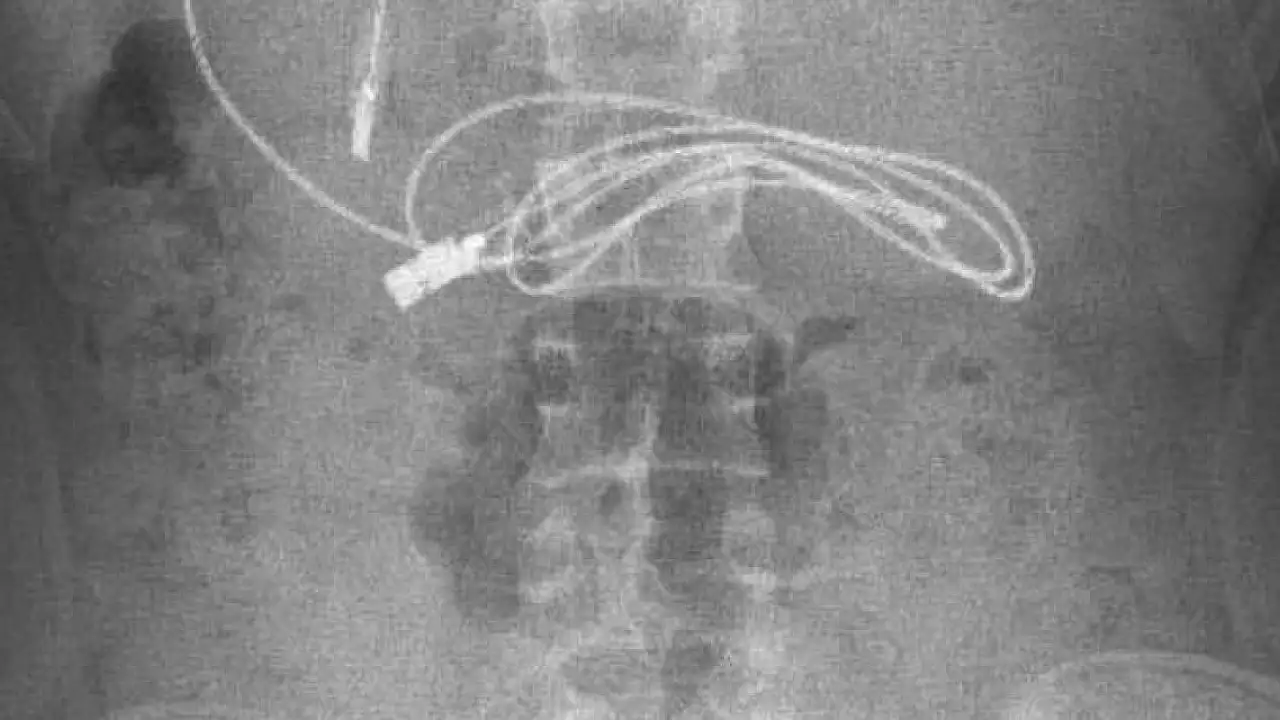

Çocuk, bölgede tek olan Fırat Üniversitesi Hastanesi Çocuk Gastroenteroloji Hepatoloji ve Beslenme Bölümüne sevk edildi. Burada da tetkik ve ön kontroller sonrası karnında yaklaşık 1 metre uzunluğunda düğümlü şarj kablosu ve lastik toka olduğu belirlenen 15 yaşındaki çocuğun tedavisine başlandı. Gastroenteroloji Hepatoloji ve Beslenme Bilim Dalı Başkanı Prof. Dr. Yaşar Doğan ve ekibi tarafından yapılan endoskopik operasyon sonucu Y.K.'nın karnında bulunan telefon şarj kablosu ve toka çıkarıldı. Kablonun düğümlü olduğunu ve ince bağırsağa dolandığı için zorlandıkları belirten Prof. Dr. Doğan, başarılı geçen operasyon sonrası hastayı taburcu ettiklerini ancak ilk kez böyle bir vaka ile karşılaştıklarını kaydetti.

Hasta hakkında bilgi veren Prof. Dr. Yaşar Doğan, "Hasta bize Diyarbakır'dan geldi. Orada yapılan incelemesinde karnında bir kablo yuttuğu ifade edildi. Oradaki hekim arkadaşlarımız bizi aradı. Biz de hastayı gerekli olan işlemleri yapmak üzere çağırdık. Hasta geldikten ve hazırlığı yapıldıktan sonra endoskopik işlemle gerekli olan müdahaleyi yaptık ve görüldüğü üzere kablo ile yanındaki saç tokasıyla birlikte çıkardık. İşlemden sonra hastada herhangi bir problem gelişmedi ve hastayı sağlıklı bir şekilde gönderdik" dedi.

Kablonun siyah renk almasının nedeni, mide asidi ile uzun süre temas olmasında dolayı bir renk değişikliğine uğramış. Bu tür vakalarla çok karşılaşıyoruz fakat böyle bir kablo yutan hasta ile ilk kez karşılaşıyoruz. Dolayısıyla bize ilginç gelen hastaydı. Açıkçası biz de işlem yaparken biraz zorlandık. Çünkü kablonun bir kısmı ince bağırsağa girmişti ve kabloda düğümlenme vardı. Bu düğümlenme olduğundan dolayı bağırsakla yapışıklık meydana getirmişti. Onu çıkarırken biraz zorlandık ama çıkarma esnasından herhangi bir komplikasyon gelişmedi" diye konuştu.